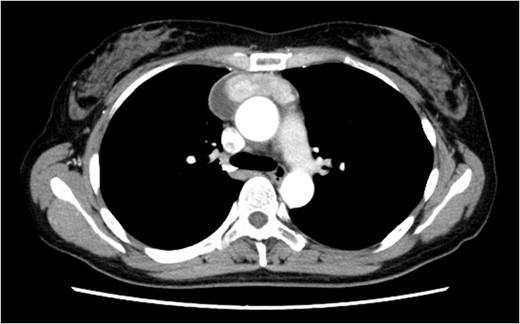

Under general anesthesia, she underwent total thymectomy via median sternotomy. Her post-operative course was uneventful and there was no visible chyle leakage from the chest drainage tube. On post-operative day 2, the chest drainage tube was removed. The chest X-ray on post-operative day 7 revealed no massive pleural effusion (Fig. 2), and she was discharged on the day. The final pathological diagnosis was a Type A thymoma with Masaoka’s Stage I.

Chest X-ray on post-operative day 7 revealing no massive pleural effusion.